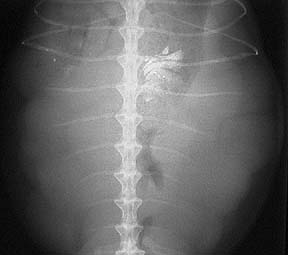

The numerous eggs in this female are a little easier to visualize

Our digital radiography machine gives us substantially better radiographs than the two above. Even though there are other factors like the amount of calcium on the eggs, and whether they are pre or post ovulatory, the difference between the old way and new way of taking radiographs is significant.

This side view is called a lateral view. The R market means this iggie was laying on her right side